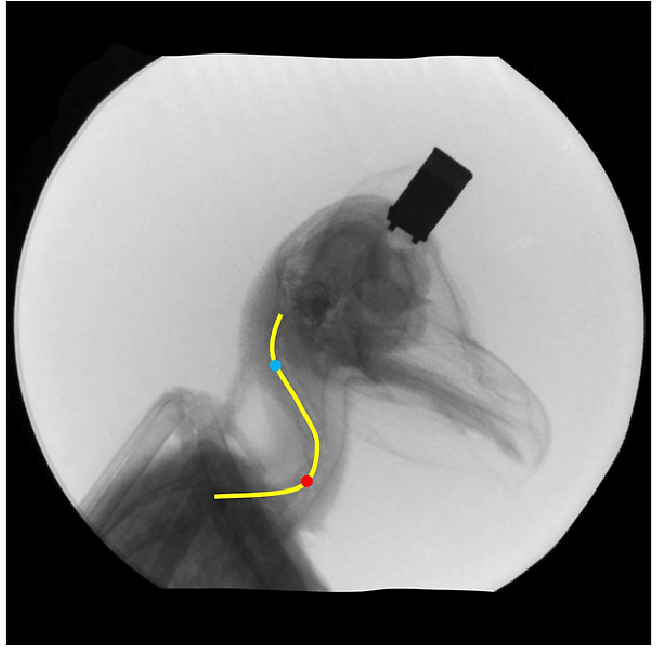

사람은 목에 7개의 뼈가 있는데, 부엉이는 그보다 훨씬 많은 14개의 목뼈를 가지고 있어요!

다만 완전한 360도는 아니고 최대 270도까지 돌릴 수 있다고 해요.

신기하게도 부엉이는 목을 그렇게 돌려도 혈액 순환이 원활하게 이루어지도록 설계된 특수한 혈관 구조를 가지고 있어요.

목뼈 주변에 넉넉한 혈액 저장소가 있어서 머리를 돌릴 때도 두뇌로 가는 혈액 공급이 끊기지 않는답니다.